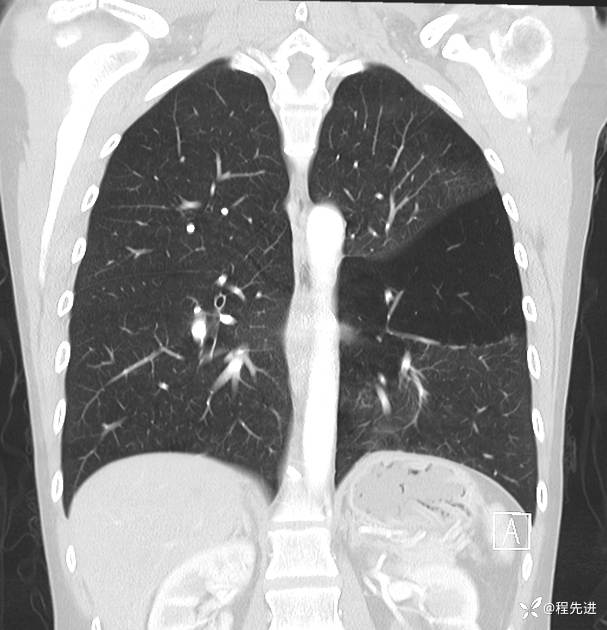

病例【心胸】特别精彩病例|下胸部疼痛3天,这个肺气肿怎么啦

患者性别:女

患者年龄:25岁

简要病史:下胸部疼痛3天

CT增强: